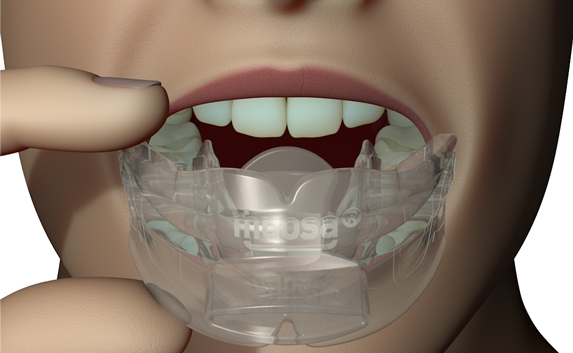

Myosa® for TMJBDS® Stage 1 Hybrid - S1H

Establish a functional airway and permits active exercises

The Myosa® for TMJBDS® S1H is specifically designed for patients who are breathing and disordered sleep (BDS) primary with moderate to severe BDS as indicated by a Breath Hold Time (BHT) of 20 or less. These patients may or may not have TMJ disorders, but due to the severity of their BDS, they require immediate improvement of their airway. The features of the appliance not only work to open the airway, but also allow patients to undertake initial exercising of the lip, tongue and airway muscles. Progress to the S1 when the patient’s BHT reaches 20 seconds or more.